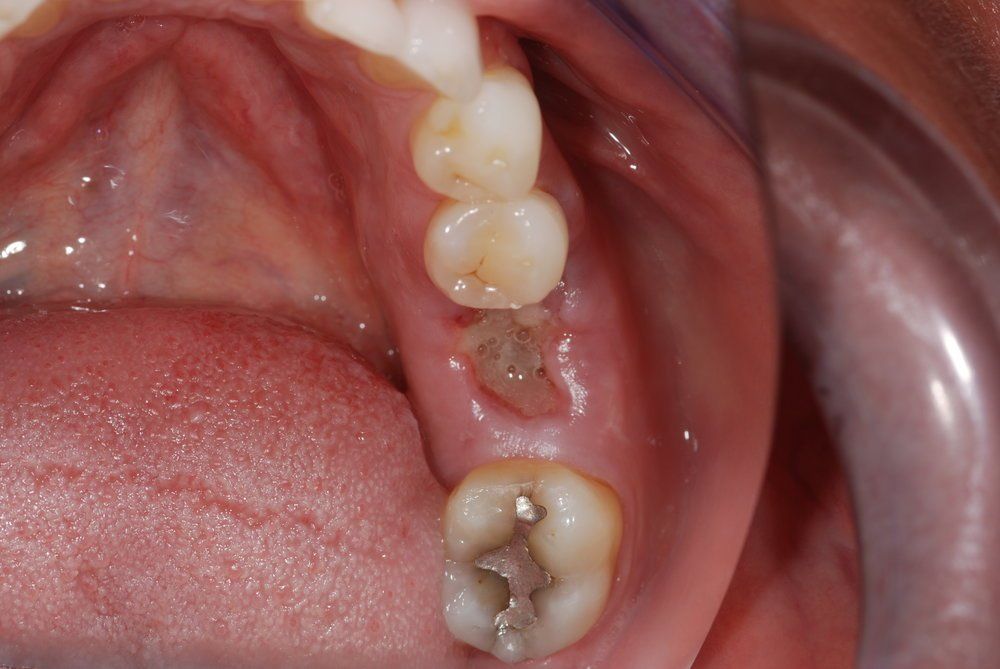

Unfortunately, it can be the case that a tooth (or teeth) are so badly damaged by trauma, bacteria, or tooth decay that removal is the only option. In this case, we recommend that a patient has dental implants inserted to replace any missing teeth. Modern dental implants are long lasting, strong, and look, feel, and function just like real teeth.

At the Dental Innovations clinic in Wasilla, AK, we specialize in single and multiple implant restorations. Our team can use a wide range of implant systems to provide patients with a full mouth of even, strong teeth. Contact our dental clinic today to arrange a consultation to discuss what dental implants may be the best for you.